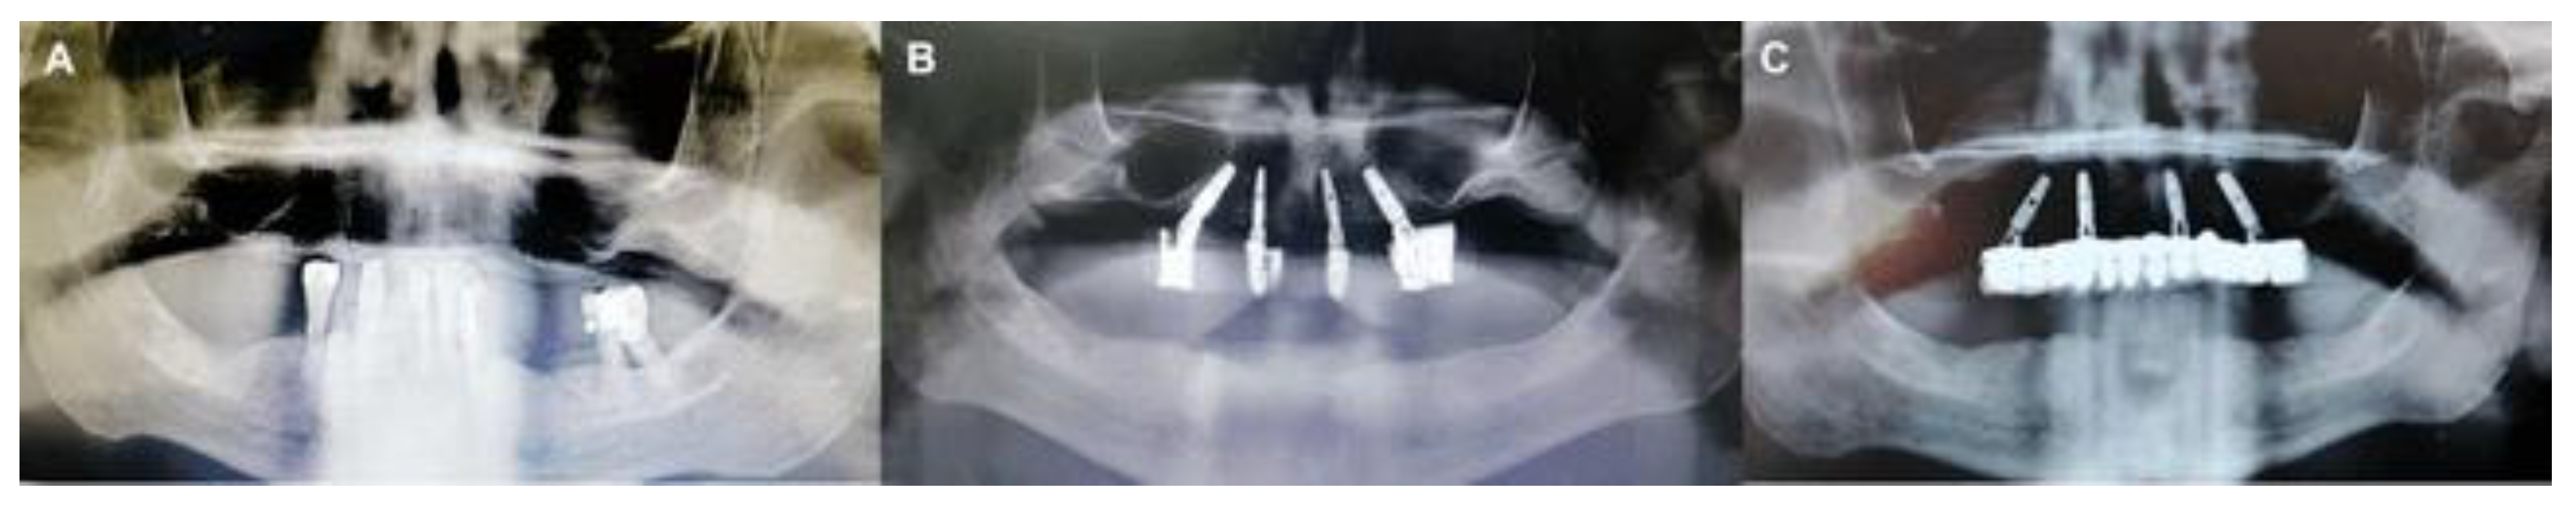

Figure 8. A. Pre-operative panorama, B. Post-operative panorama with a provisional prosthesis, C. Post-operative panorama with final prosthesis.